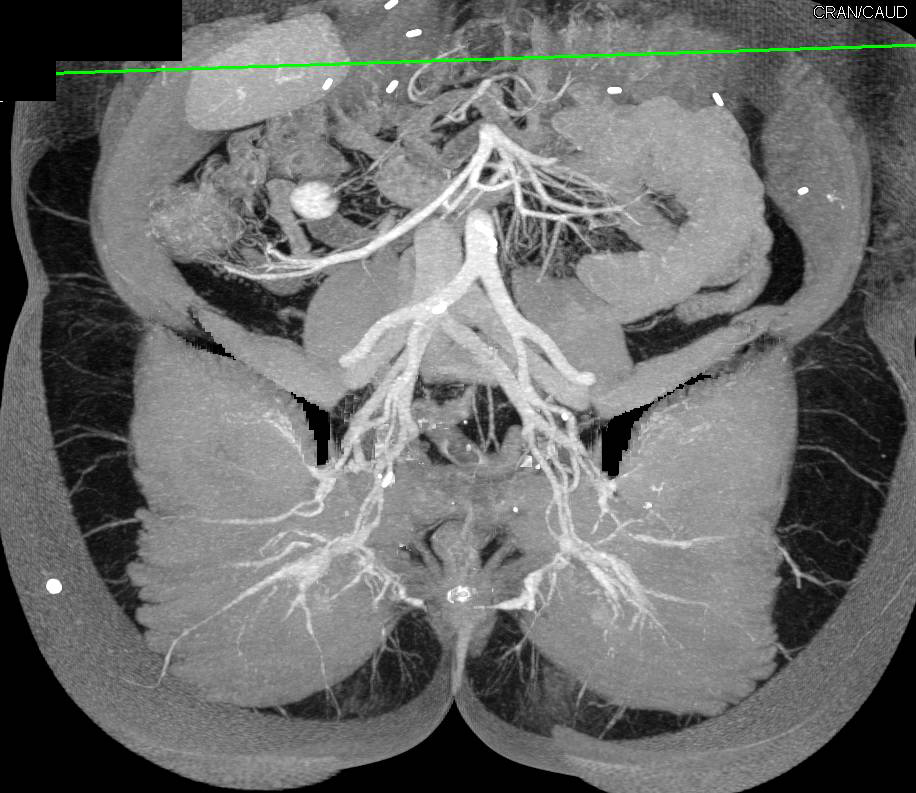

Focal Aortic Dissection